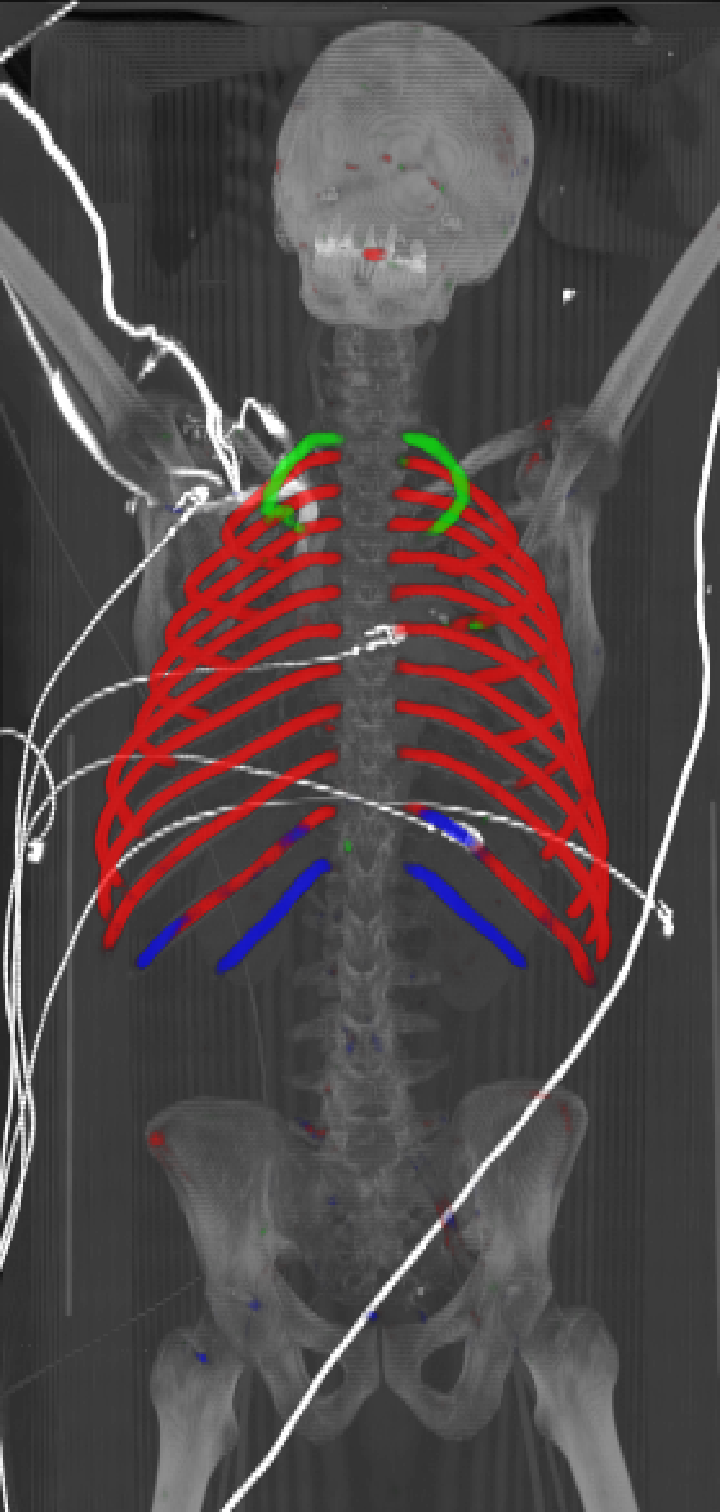

As can be seen from Table 2, we obtain overall good performance for the overall rib detection captured for example with an mean Dice of 0.84. Let us remark that for thin objects, such as the dilated rib centerlines, the Dice score constitutes a rather sensitive measure. The results indicate that detecting the first and twelfth rib pairs is more difficult for our network. While extraction of the first rib is more challenging due to, e.g., higher noise in the upper thorax or other bony structures in close vicinity (clavicle, shoulder blades, vertebrae), the twelfth rib can be extremely short and is easily confused by the neighboring ribs. For further illustration, Figure 4 shows the results on selected representative cases. Generally, the ribs are well detected without major false responses in other structures - despite all the different challenges present in the data. The color coding highlighting of the multi-label detection reveals that first and twelfth are mostly correctly detected. In few cases the network wrongly generated strong responses of the classes first rib or last rib for voxels belonging to the second or eleventh rib pair.

Refer to caption

Figure 4: Maximum intensity projections (MIP) of selected CT volumes overlaid with the multi-label output of the neural network (green: first rib; red: intermediate rib; blue: twelfth rib). The selected case above display common difficulties which are inherent in the data set, such as pads (a) or cables (b), internal devices such as pacemakers (c), stents (d), spinal (e) and femural/humeral implants (f), injected contrast agents (g), patient shape variations such as scoliosis (h), limited field of views (FOVs), i.e. partly missing first (i) or twelfth rib (j).